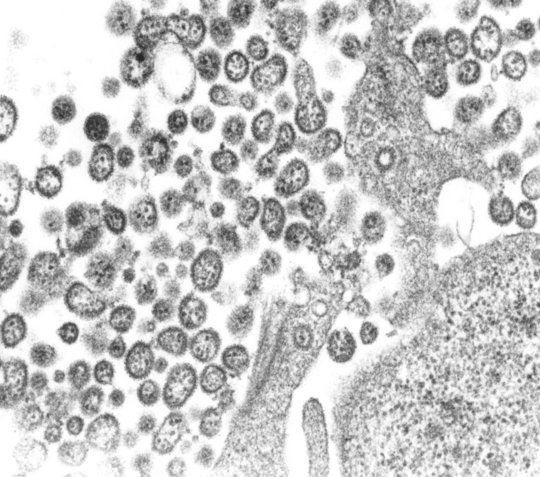

Das BNITM bringt insbesondere Viren aus tropischen Regionen ein, die in den hauseigenen Sicherheitslaboren der Schutzstufen 3 und 4 gelagert werden. Insgesamt sind aktuell rund 200 virusbezogene Produkte verfügbar, darunter:

- Lassa-Virus-Stämme aus Westafrika (2004–2014),

- verschiedene Filoviren, z. B. Ebola- und Marburg-Virus,

- Krim-Kongo-Fieber-Virus aus Afghanistan,

- Chikungunya-, Dengue-, und Gelbfieber-Viren,

- seltene Arenaviren (u. a. Machupo, Guanarito) und Hantaviren (z. B. Sin Nombre, Tula).

Ein Großteil dieser Viren stammt aus Patientenmaterial – etwa aus der Zeit der Ebola-Epidemie in Westafrika 2014–2016 oder von Lassa-Virus-Ausbrüchen. Besonders gefragt sind virusabgeleitete Produkte wie gereinigte RNA, die unter sicheren Bedingungen für Diagnostik und Testentwicklung genutzt werden können.